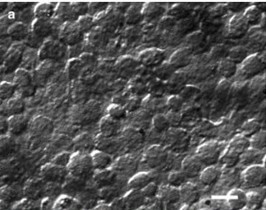

AT2基因敲除細胞介紹: 近端小管是腎臟腎臟管系統的一部分,涉及腎素 – 血管緊張素系統的調節。該區域的細胞有助於調節鈉和體積的體內平衡以及調節全身血壓。蛋白質血管緊張素II(Ang II)及其受體AT1和AT2是本系統研究最多的蛋白質之一。AT2敲除永生小鼠腎近端小管細胞係是從攜帶猿猴病毒SV40大T抗原的熱不穩定突變(tsA58)的小鼠分離的條件永生小鼠腎近端小管細胞。 SV40大T抗原的功能表達是通過在容許溫度(33℃)的培養基中培養含有IFNγ的培養基來誘導的。在不允許的溫度(37℃-39℃)下,細胞不再增殖。當與野生型(貨號T0624)和其它血管緊張素受體(Ang II)缺陷型細胞系AT1A – /(貨號T0626)配對時,將AT1B – / – (貨號T0627)和AT1A – / – AT1B – / – (貨號T0628),這些細胞系在研究近端小管區域流體和電解質運輸的有價值的工具。